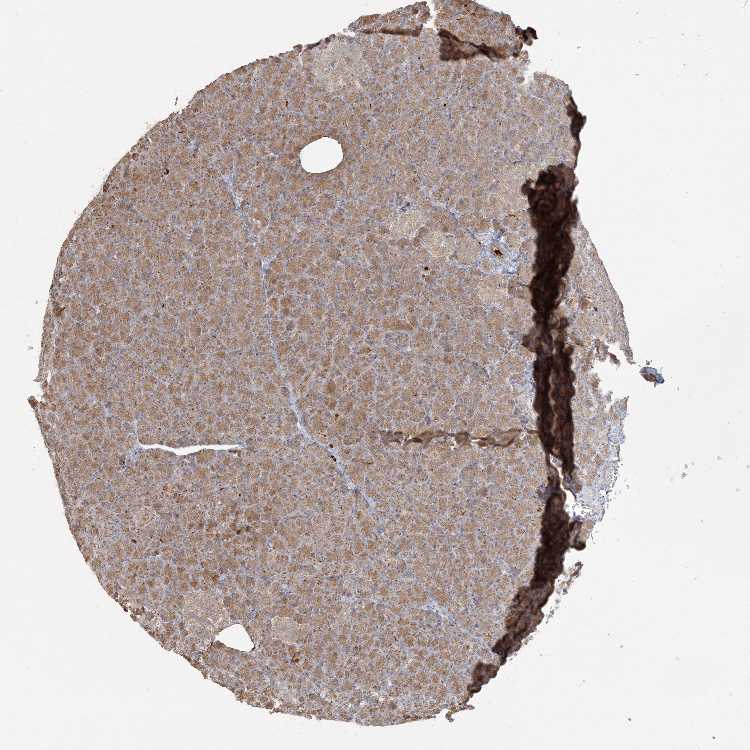

PANCREAS - Antibody stainingi

Antibody staining in the annotated cell types in the current human tissue is reported as not detected, low, medium, or high, based on conventional immunohistochemistry profiling in selected tissues. This score is based on the combination of the staining intensity and fraction of stained cells.

Each image is clickable and will lead to virtual microscopy that enables deeper exploration of all samples and also displays staining intensity scores, fraction scores and subcellular localization as well as patient and tissue information for each sample.

Antibody HPA035471

Exocrine glandular cells Medium

Pancreatic endocrine cells Medium